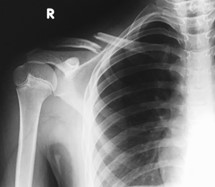

- Your child has fractured (broken) their clavicle (collar bone)